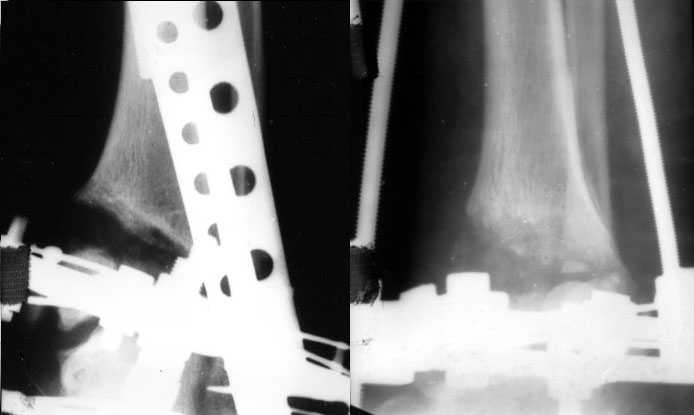

Аппаратом можно сделать все минимально инвазивно и травматично, вырастить клиновидный регенерат после чрескожной остеотомии через один или два разреза 0,5 см. В приложении похожий по локализации случай, только более давние последствия травмы с замыканием части зоны роста, деформация побольше, плюс укорочение голени было.